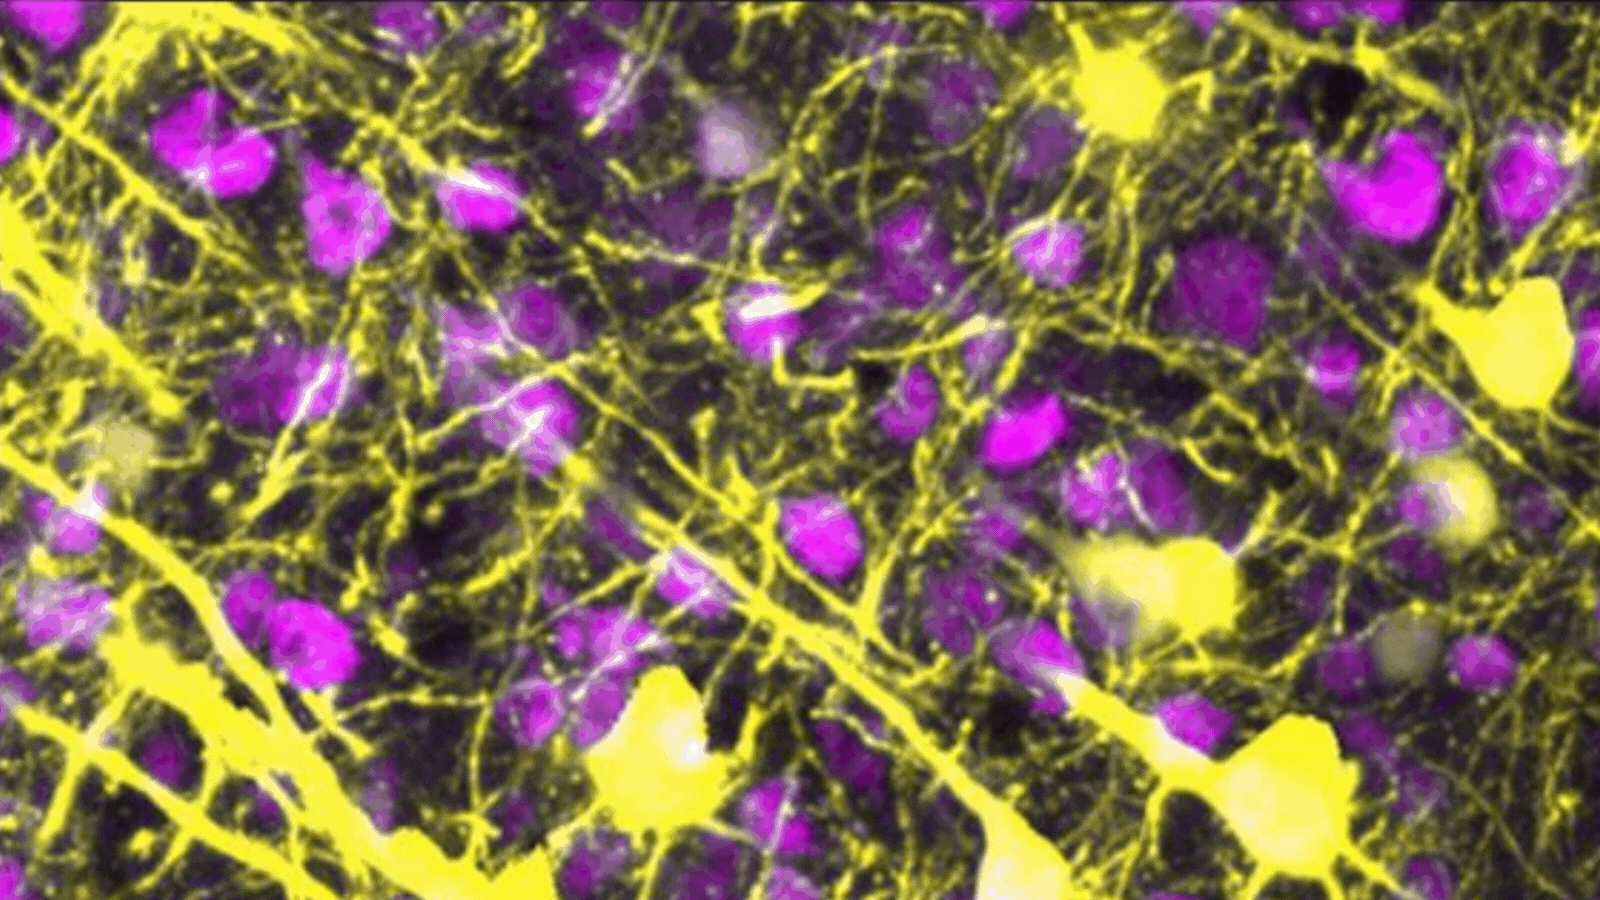

A microscopic image showing brain neurons and their elongated conenctions to one another. This image shows healthy connections between the neurons.

The brain’s neurons (yellow) connect with one another using a vast network of neural wires, called neurites.